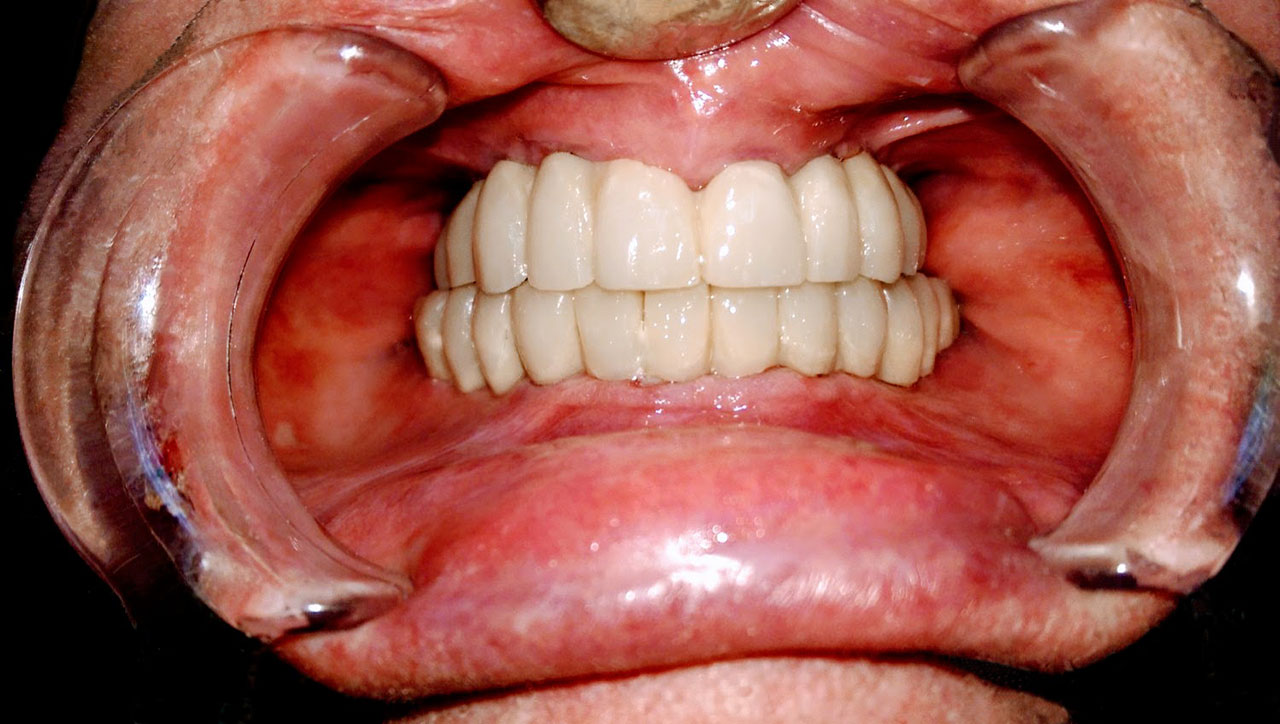

• esettanulmany-04

Impantáció előtt, súlyos fogágy pusztulás, gyulladás látható.

• esettanulmany-06

Impantátumok a végleges híddal.